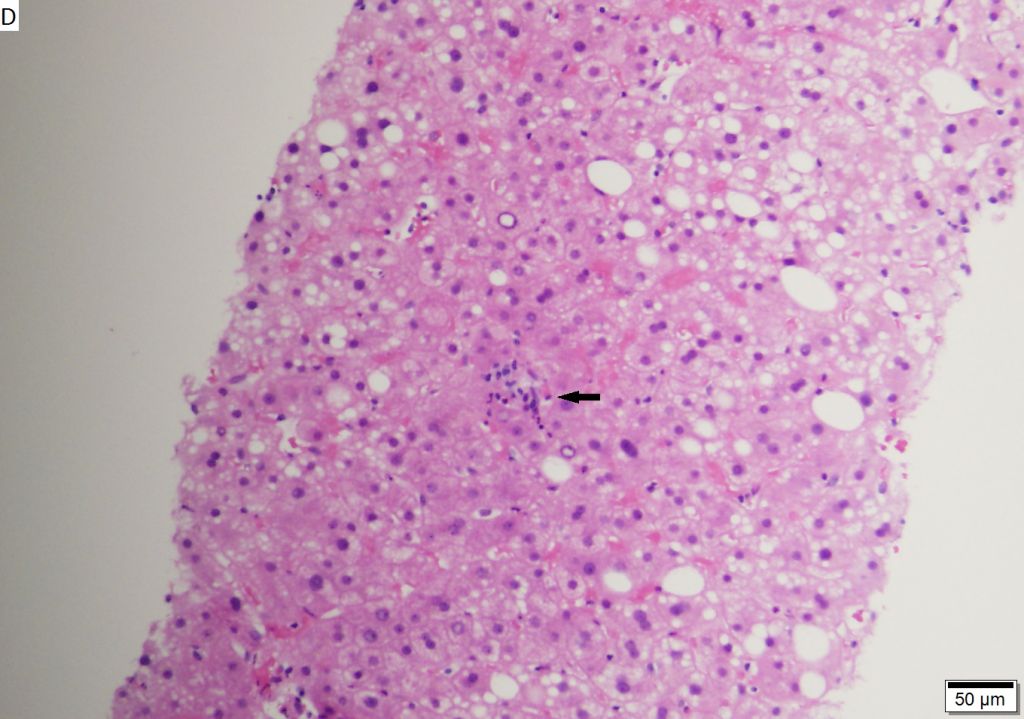

То, как вирус поражает печень больного, напоминает настоящий боевик или триллер. По кровотоку патоген достигает печени, на поверхности которой находится особый вид полипептида, уязвимый перед крупным белком вируса гепатита B. Связываясь с ним, гепатит проникает в центр клетки, скидывая на ходу свою оболочку и высвобождая ДНК. Образно говоря, пользуясь полипептидом как отмычкой, вирус осуществляет взлом и захватывает клетку. Со временем этот процесс распространяется по всей печени, и обычно он занимает от 3 до 6 месяцев.

Несмотря на столь циничный захват, вирус не убивает клетки печени. Это делает наша иммунная система, которая активирует Т-лимфоциты, или Т-киллеры. Именно они наносят критические повреждения органу. Воспаление как сигнал срабатывает и для других иммунных клеток, что еще больше осложняет ситуацию в тканях печени. Пациент может долго не знать о своей болезни, так как в первые полгода происходящие в печени процессы могут себя никак не проявлять. Среди начальных признаков гепатита B − головные боли, тошнота. Самыми характерными признаками инфекции являются изменение цвета кожи, мочи и кала.

Гепатит может пройти самостоятельно, однако, если спустя шесть и более месяцев после перенесенного заболевания в крови все еще можно обнаружить антиген HBsAg, то считается, что инфекция перешла в хроническую форму. А это уже сопряжено с высокими рисками развития цирроза и рака печени. Так, по статистике, цирроз печени у больного может появиться с вероятностью 8–20% в течение следующих пяти лет. В дополнение к этому, каждый год в 1–5% случаев на фоне цирроза может развиться еще и рак печени.